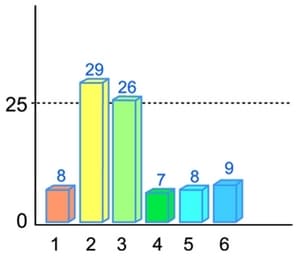

Figure 6 presents the total deviation from the electric potential norm at various stages of the experiment.

Figure 5 illustrates the changes in the electric potential of the circulatory systems control points when under the influence of electromagnetic radiation from a mobile phone (second column in the diagram) in comparison with the baseline radiation (first column) and radiation with the Aires Shield (third column).

Note not only the sharp reduction in the electric potential of the circulatory system under the influence of electromagnetic radiation from the mobile phone to the level of developing progressive dystrophic changes in the system, but the obvious effect of the drop in electric potential (indicated in red), which indicates pronounced astenization and a distruption of neuroendocrinal regulation and vegetative balance.

The Aires Shield electromagnetic anomaly neutralizer both fully restores the electric potential and eliminates the progress of astenization, saving resources for the body.

The behavior of the total deviation from the electric potential norm clearly illustrates the affect of a mobile phone’s electromagnetic radiation and the Aires Shield electromagnetic anomaly neutralizer on the activity of organs and body systems. The value is 0 at the norm.

It can be seen that a three-minute mobile phone conversation reduces the activity of organs and tissues in basically healthy people by an average of 30%, which coincides with data from the WHO. People with more pronounced electric potential deviations (up to 40% from the norm), the negative affect of the mobile phone’s electromagnetic radiation is more apparent and reaches 50%, but the Aires Shield electromagnetic anomaly neutralizer not only protects the body from the affects of the man-made radiation, it also promotes restoration of the disrupted activity.